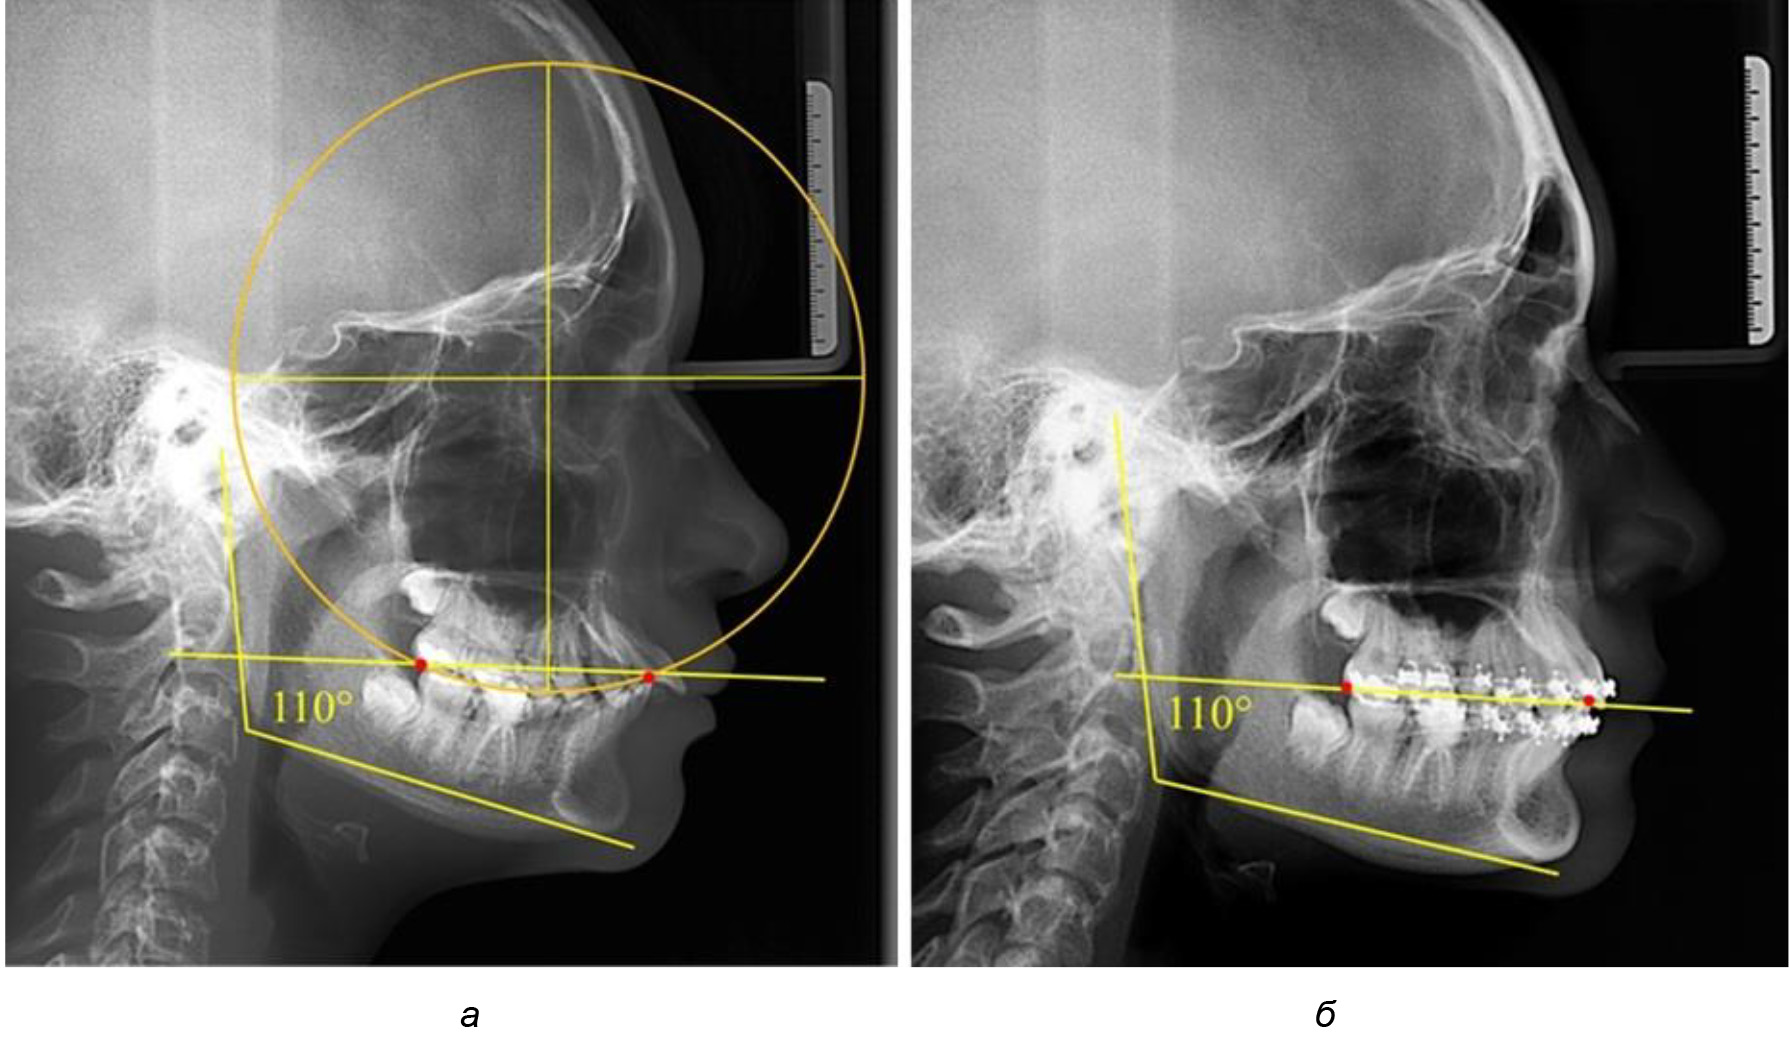

При анализе латеральных ТРГ устанавливали реперный окклюзионные точки в переднем и боковом отделе. Передняя точка устанавливалась на режущем крае нижнего медиального резца, которую в клинике ортодонтии обозначают как vPOcP. Дистальная точка второго нижнего моляра обозначалась как hPOcP. Измеряли расстояние между окклюзионными точками, что определяло сагиттальный размер окклюзионной линии. Использование программ PowerPoint позволило проводить окружность, проходящую по линии смыкания зубов через окклюзионные точки. Измеряли радиус окружности. Учитывая вариабельность размеров окклюзионной линии и радиуса окружности, определяли относительный показатель через отношение радиуса круга к длине сагиттального размера окклюзионной линии. Глубину окклюзионной кривой измеряли от точки наибольшей выпуклости до окклюзионной линии (рис. 1). На ортопантомограмме (ОПТГ) также соединяли окклюзионные точки правой и левой стороны и измеряли глубину окклюзионной кривой от точки наибольшей выпуклости до окклюзионной прямой линии. Результаты глубины кривой Spee сравнивали по данным ТРГ и ОПТГ.

Рис. 1. Метод определения кривой Spee на ТРГ (а) и на ОПТГ (б)